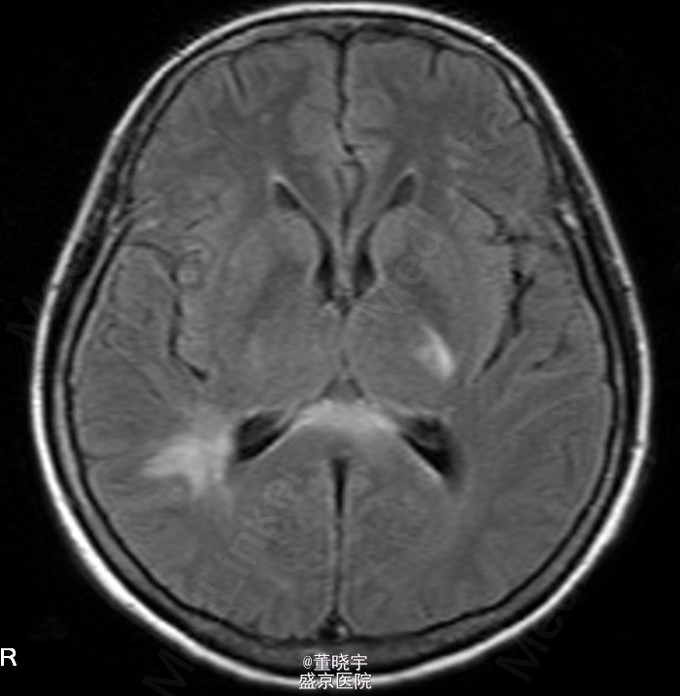

神经系统专科查体:神清语明,双瞳等大正圆,D=4.0mm,对光反射迟钝,视力丧失,双眼球各向运动充分,无复视及眼震,额纹对称,双侧鼻唇沟对称,伸舌居中,转颈有力,四肢肌力Ⅴ级,肌张力正常,双上肢指鼻准确,双下肢跟膝胫试验稳准,BCR L++R++, TCRL++R++,PSRL++R++,Babinski征L+R+,Hoffmann征L-R-,颈强,双掌颏反射(+)。 辅助检查:腰穿压力200mmH2O,细胞总数28*10^6/L,白细胞24*10^6/L,氯化物118.0mmol/L,糖2.41mmol/L,蛋白2.1g/L。 视觉诱发电位:双侧视通路传导障碍。 颅脑MRI见上。 核抗体(ANA)阳性;抗SS-A及抗SS-B抗体均阳性;IgG、IgA升高;补体 C3、C4下降。

诊断:原发性干燥综合征合并中枢损害 处理:静脉点滴丙种球蛋白治疗,临床症状稳定后出院口服强的松片10毫克/天。

半年后患者再次入院复诊,复查颅脑MRI提示新增病灶,但风免相关化验未见改变,急性长期口服激素治疗。 讨论:原发性干燥综合症(pSS)是一种以唾液腺和泪腺腺体淋巴细胞浸润和破坏为特点的自身免疫性疾病,临床主要表现为眼干、口干。腺体外表现主要是由于类似的单核细胞浸润或血管炎引起。CNS-SS的发病率及其颅脑MRI表现目前仍存在争议,有文献报道CNS病变发生率为0%-60%[1]。既往的一个400例患者大样本研究发现,只有1%患者合并CNS并发症。 CNS-SS的临床表现多样,脑部病变包括局灶性和弥漫性病变,局灶性病变主要表现为局部感觉和运动异常、失语、癫痈发作、构音障碍和视觉减退等;弥漫性病变主要表现为亚急性或急性脑病、无菌性脑膜脑炎、心理障碍和认知障碍等。中枢神经系统病变多隐匿起病,少部分患者呈急性或亚急性起病,部分患者同时合并有周围神经系统损害,加上部分pSS患者以中枢神经系统损害为首发症状,使得临床症状表现多样,诊断困难,极易误诊、漏诊并延误治疗。 目前对于pSS合并中枢神经系统病变治疗还没有统一的方案,大剂量激素治疗是目前临床中常用的方法之一,也有报道对于激素效果不佳的患者合并应用环磷酰胺也收到了不错的效果。静脉注射丙种球蛋白(IVIg)也是免疫相关的中枢神经系统病变常用治疗手段之一,尽管外文报道IVIg对于pSS引起的周围神经病变效果明显。